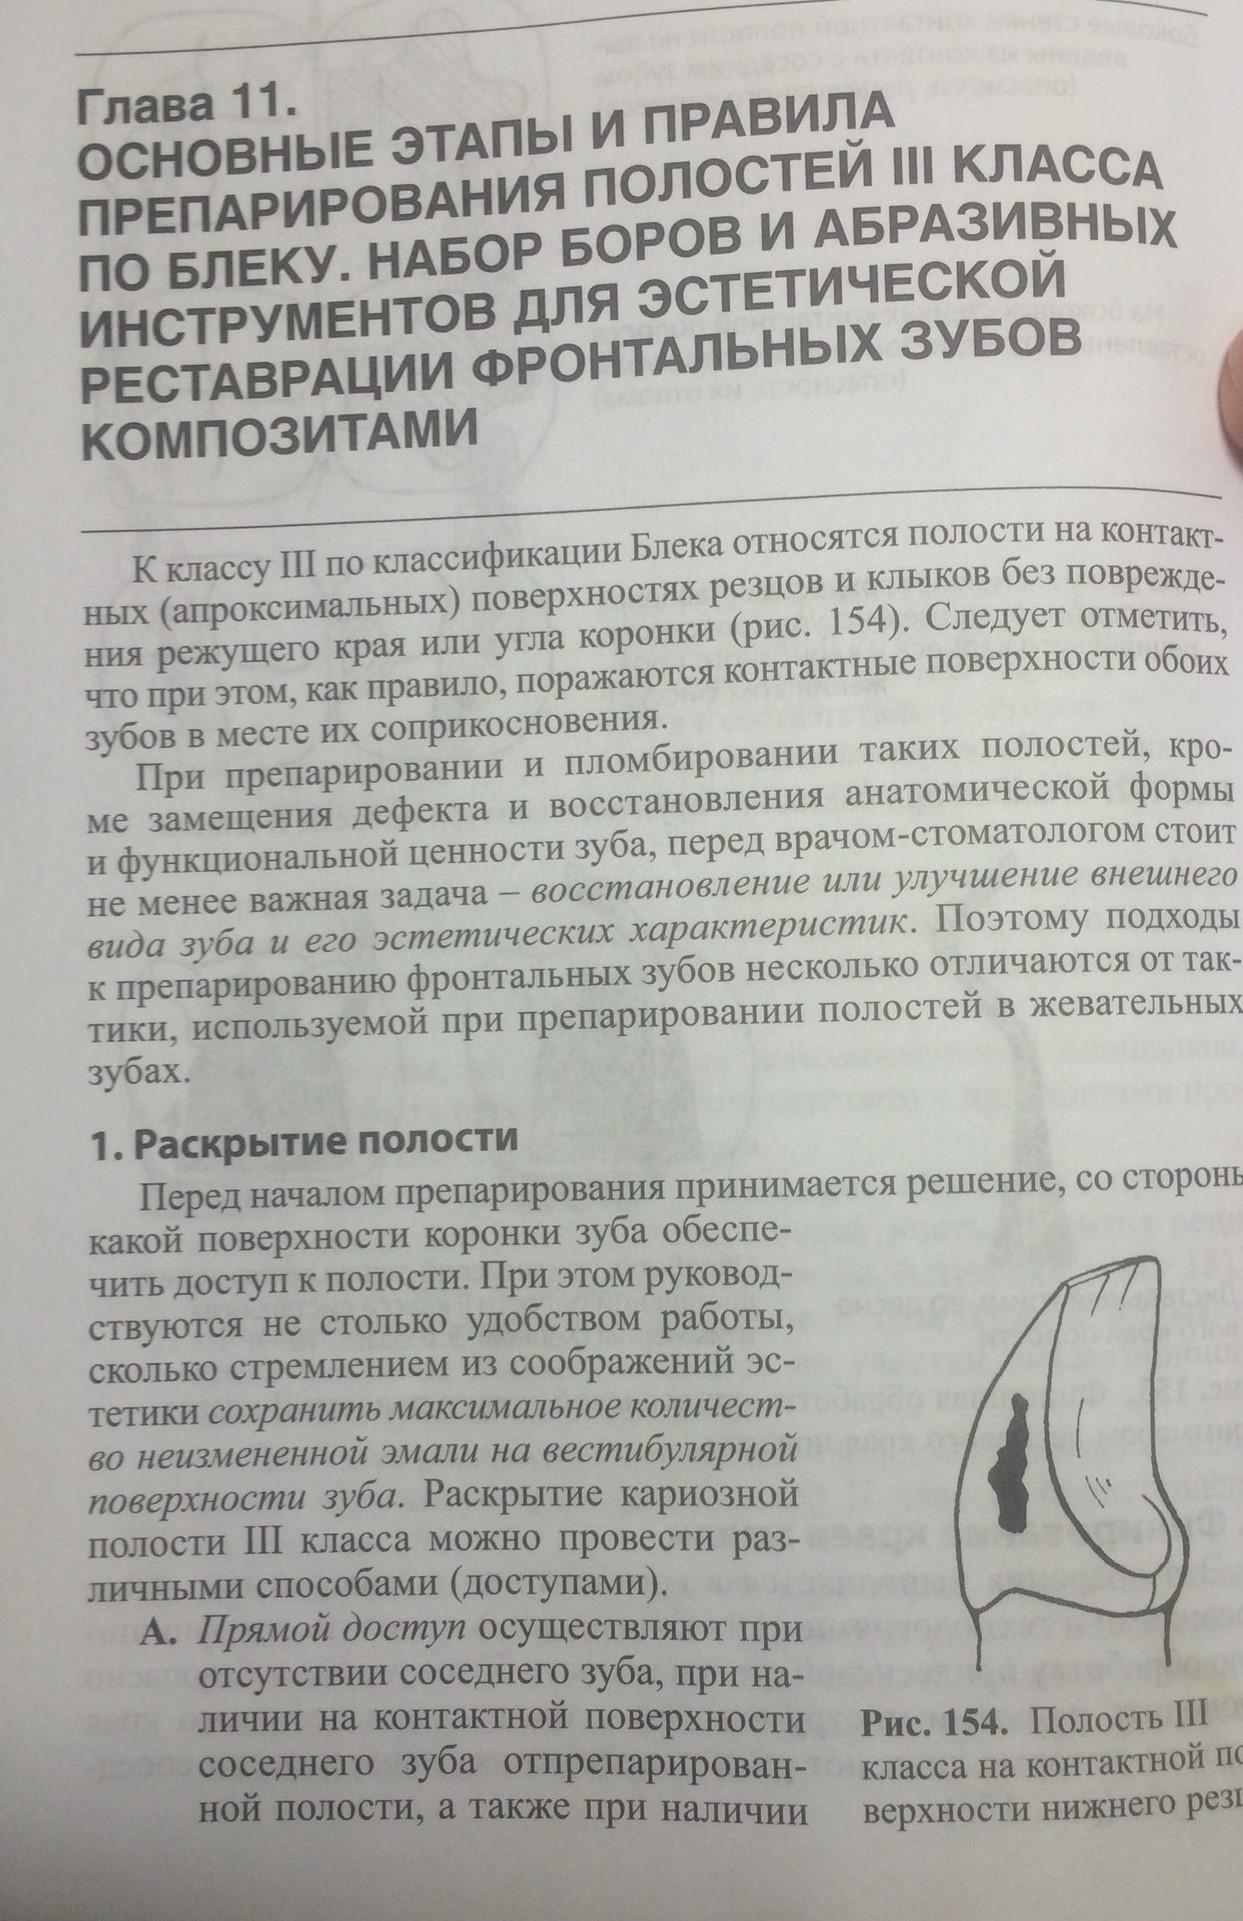

Препарирование кариозных полостей III класса: пошаговое руководство с фото

Раздел: Необычные решения